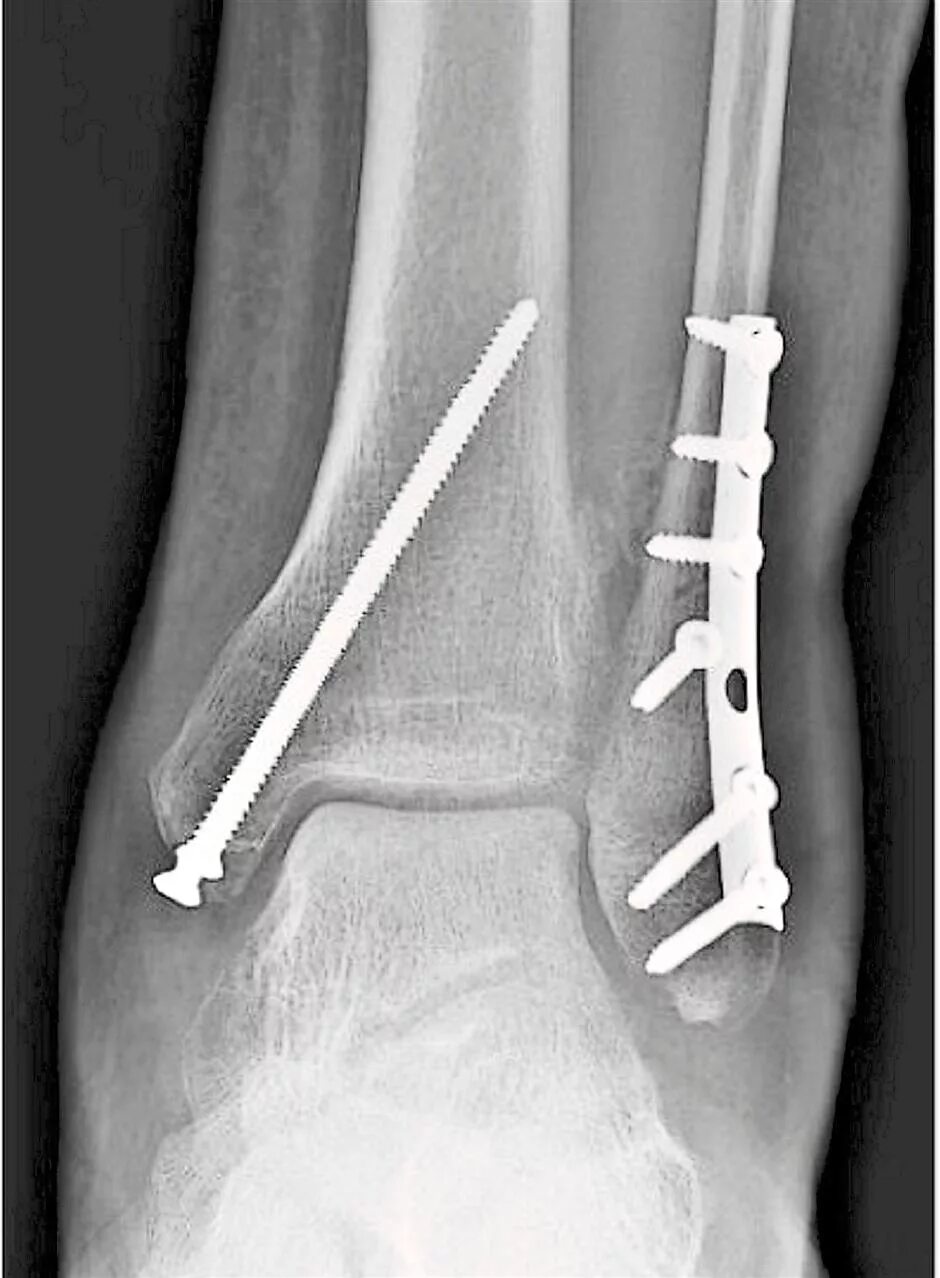

После остеосинтеза лодыжек